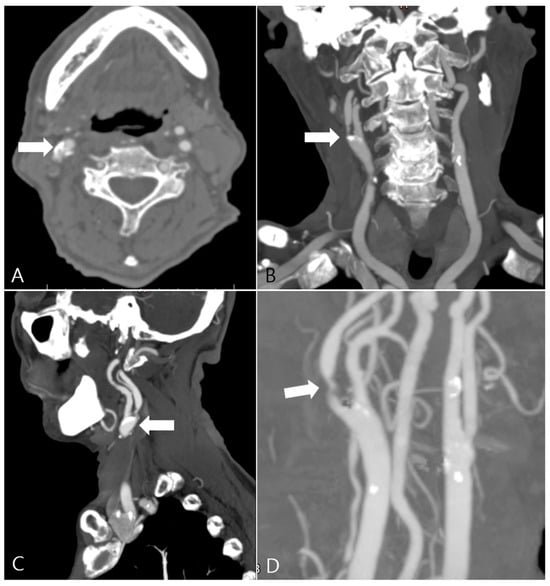

2.2. CTA Imaging Protocol

2.3. Carotid Artery 3D Model Reconstruction

2.4. Carotid Geometry Measurement